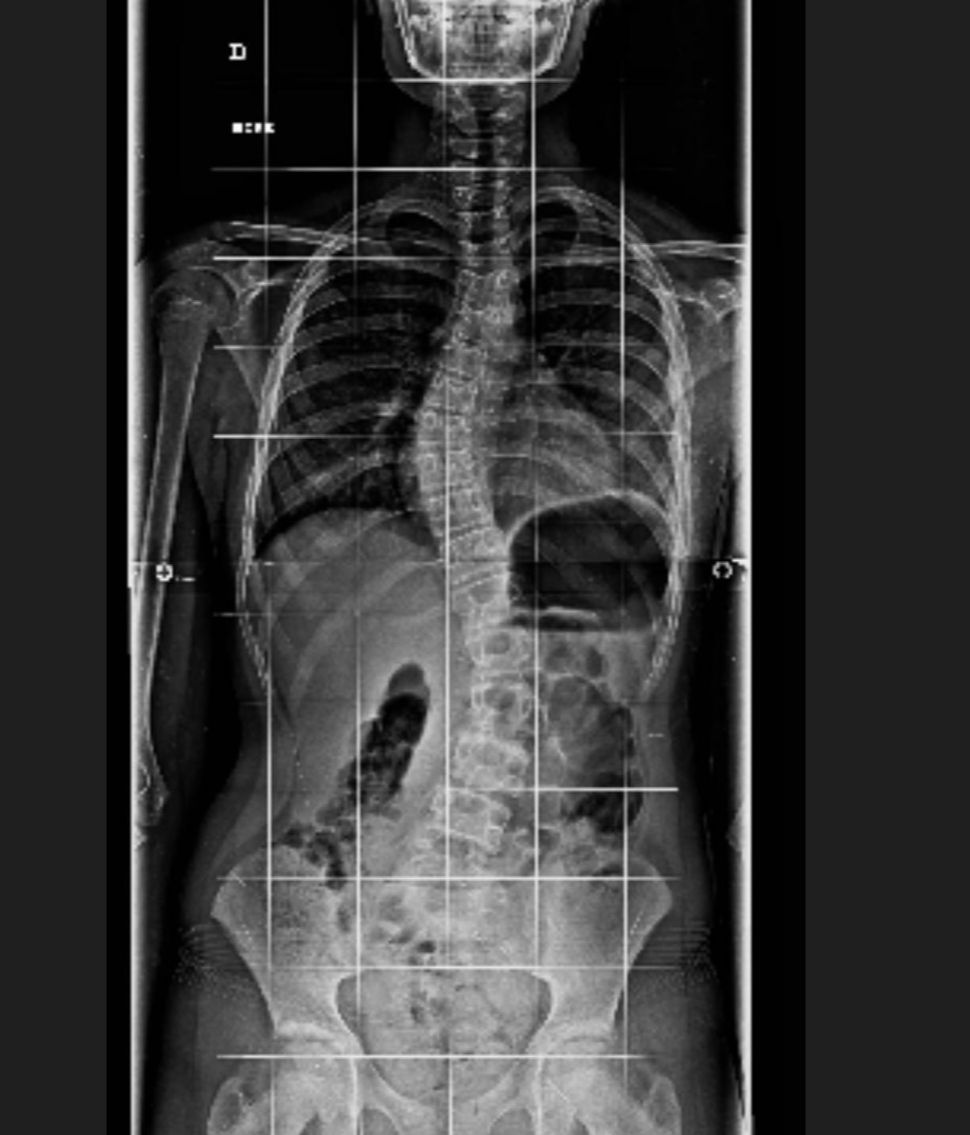

Tras solicitar ayuda, la modelo ha querido compartir la dolencia que sufre su hija mayor y el motivo de la urgencia para localizar al doctor que trate su caso. "Inés tiene una escoliosis severa. Me han recomendado este médico pero por la Seguridad Social tardaré demasiado", ha comenzado diciendo a sus seguidores, con los que ha compartido además una radiografía en la que se puede apreciar la importante curvatura que presenta Inés en la columna.

Según se desprende de sus palabras, la menor está sufriendo algunos síntomas muy molestos y de ahí la necesidad de acudir cuando antes al especialista para, por lo menos, poder paliarlos y valorar las opciones de tratamiento. "No tengo tiempo. Le duele mucho", ha dicho la modelo.